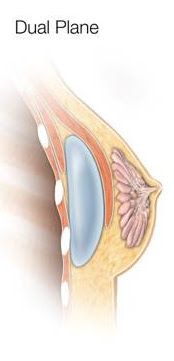

Dual Plane Implants

Dual plane placement is a lesser known implant placement, and is essentially a combination of both submuscular and subglandular options. In its simplest form, dual plane implants involve the upper pole of the implant being placed under the muscle and the lower pole of the implant sitting over the muscle, and under the breast tissue. The implant progresses from a submuscular to subglandular position. There are pros and cons to dual plane positioning:

- Many think that dual plane is the most natural implant position. This is due to reduced implant visibility in the upper pole, and greater fill in the lower pole to create a “teardrop” aesthetic.

- Dual plane implants provide greater support to the implant from the partial submuscular placement, reducing the risk of displacement.

- Dual plane allows the surgeon to tailor the implant placement according to the patient.

- Strategic dual plane placement can achieve a slight nipple elevation.

- Dual plane has a greater level of animation than under the muscle placement

- The dual plane procedure is more complex than subglandular or submuscular options.

- In patients with little-to-no breast tissue, dual plane placement may not provide the most appropriate coverage. Implant edges may be visible in the lower pole.

Dual plane placement is becoming more popular, and is generally preferred in situations of mild laxity or ptosis , constricted lower poles, and tuberous breast correction. Dual plane is generally appropriate to achieve a more teardrop-shaped look for patients with a moderate level of existing breast tissue.